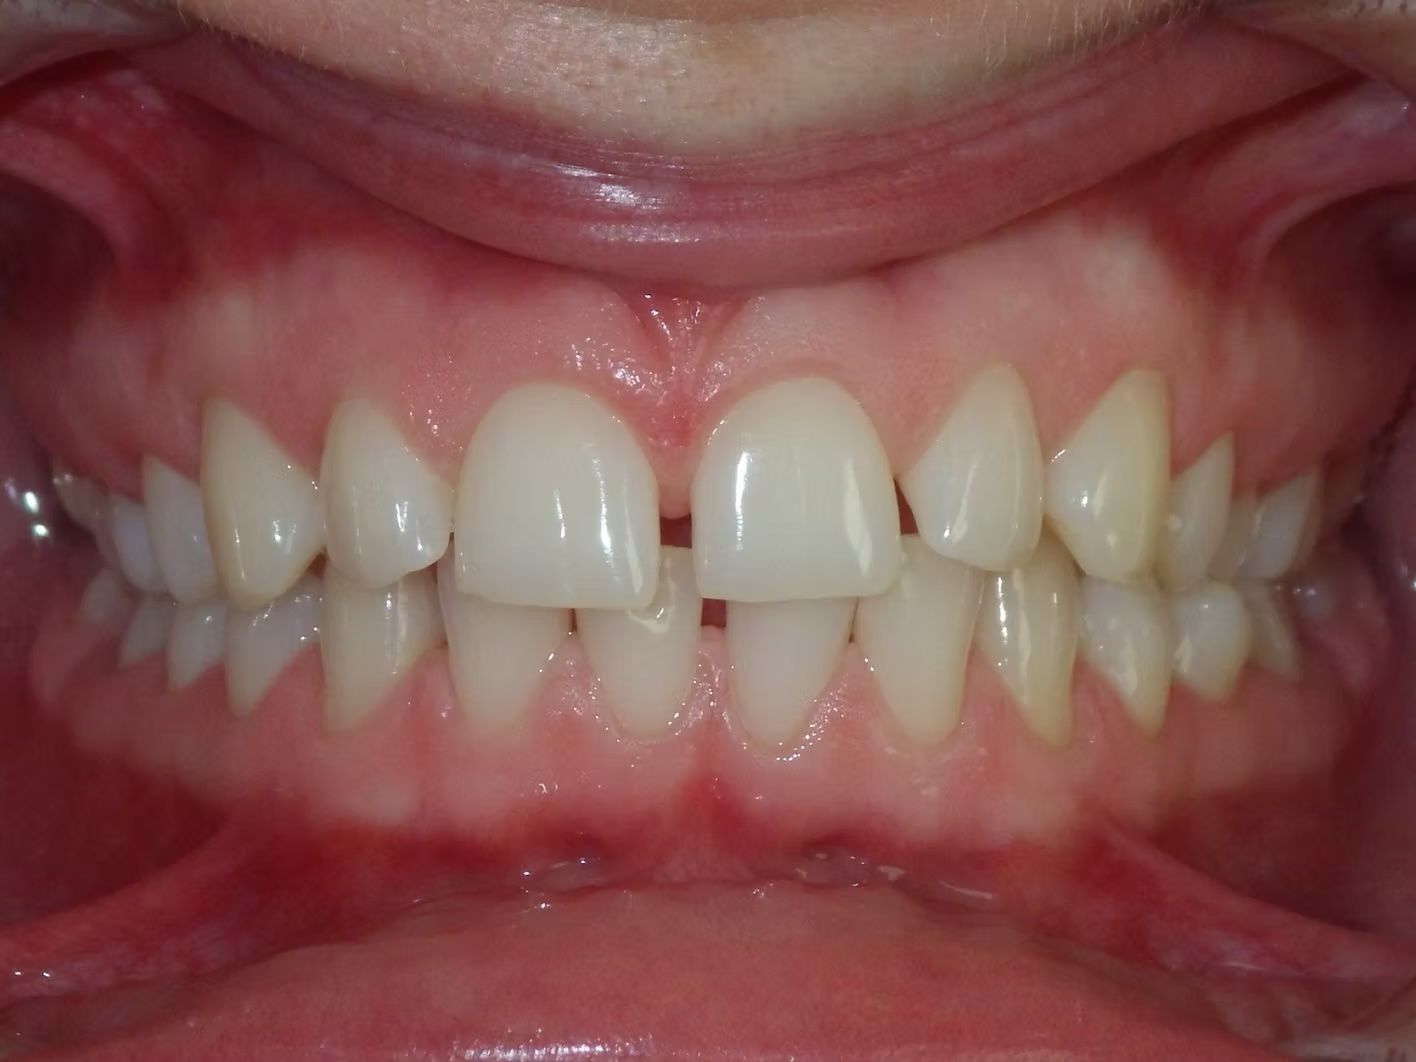

JESSIE

Jessie didn't like her spaces. She had space in the top and bottom jaws and wanted to close it. Her bite was also off on the left side and her midline was not centered. In the end, we fixed it all - doesn't she look great!